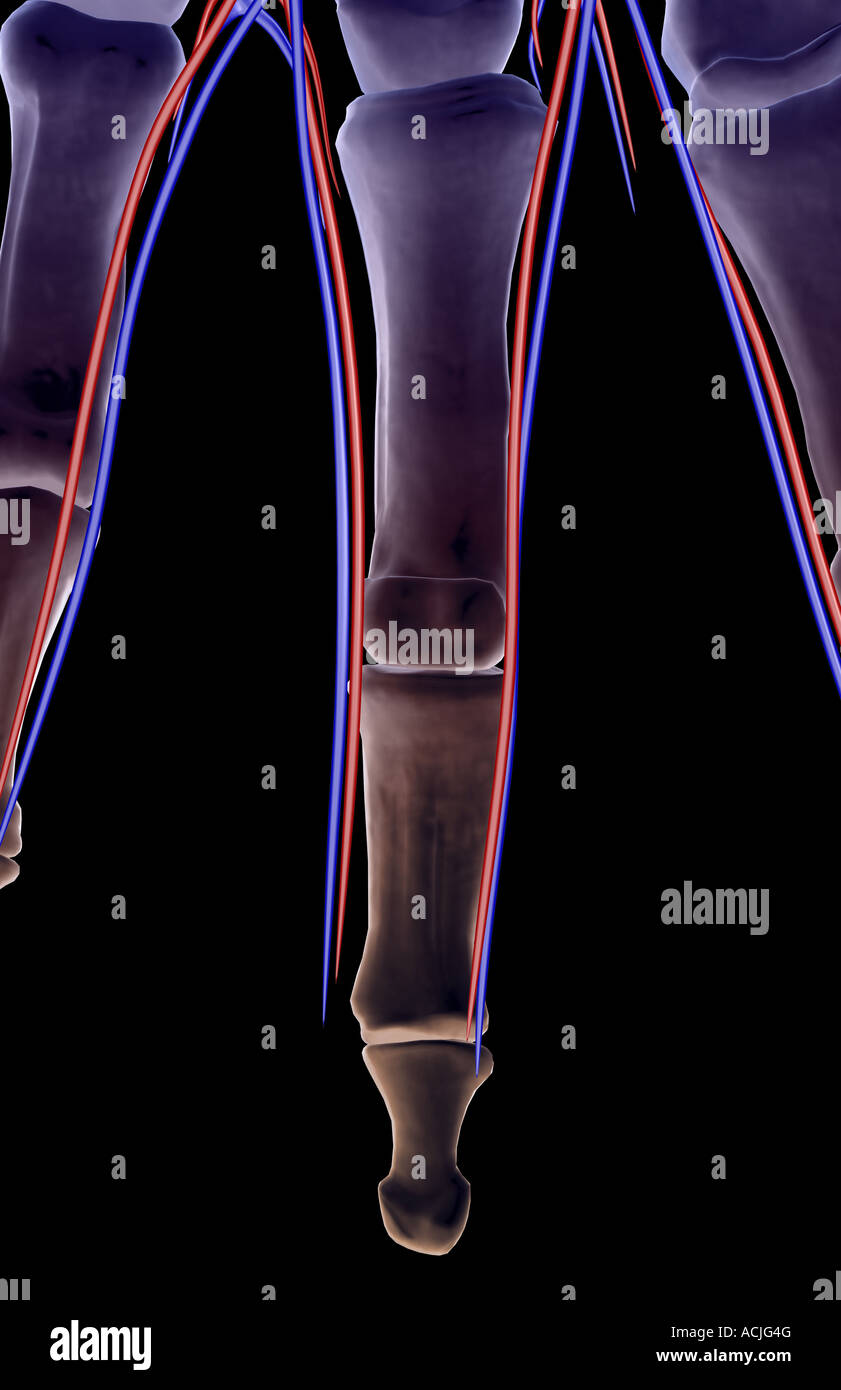

The blood supply of the fingers Stock Photohttps://www.alamy.com/image-license-details/?v=1https://www.alamy.com/stock-photo-the-blood-supply-of-the-fingers-13170351.html

The blood supply of the fingers Stock Photohttps://www.alamy.com/image-license-details/?v=1https://www.alamy.com/stock-photo-the-blood-supply-of-the-fingers-13170351.htmlRFACJG4G–The blood supply of the fingers